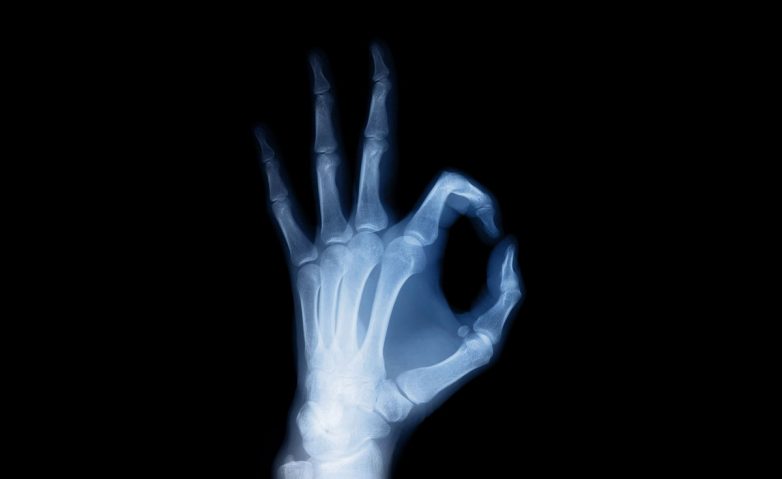

1. Рентгеновские лучи

Из любопытства поместив руку перед электронно-лучевой трубкой, в 1895 году Вильгельм Рентген и увидел ее изображение на фотопластинке, позволяющее рассмотреть чуть ли не каждую кость. Так Вильгельм Рентген открыл одноименный метод.